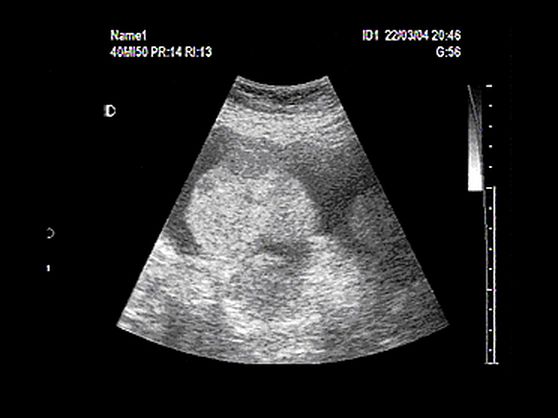

7.5. Patología anexial

Dr. A. López Cano, Dr. M. Tejada Cabrera (Cádiz)